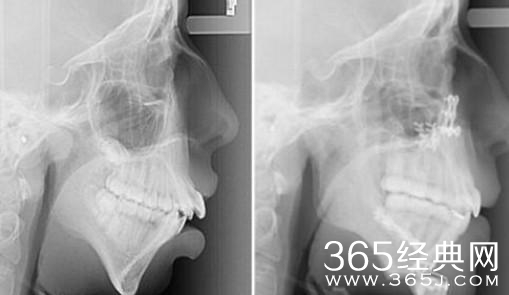

这个女孩8岁的时候下巴就开始停止生长了,因为下巴生长速度跟不上其他部位的生长速度导致脸部发育不良有些畸形,因为太过于影响美观女孩觉得去整容,只是稍微做了一下微小的调整让女孩的脸发生了天翻地覆的变化,女孩现在看起来特别的漂亮。

平时这么看的时候根本看不出来女孩有整容的痕迹,只有通过x光照才能够看到女孩有整容的痕迹,一个小小的手术就能让女孩达到这种效果真是了不起,和其他人整个脸的整容来说太值得了,女孩现在因为自己漂亮的容颜非常的开心,现在的她也非常的自信。

Baby以前的下巴和现在的下巴也存在着一定的差异性,相信这个差异性不是化妆和打扮能够改变的,看完这个女孩的微型整容过程。